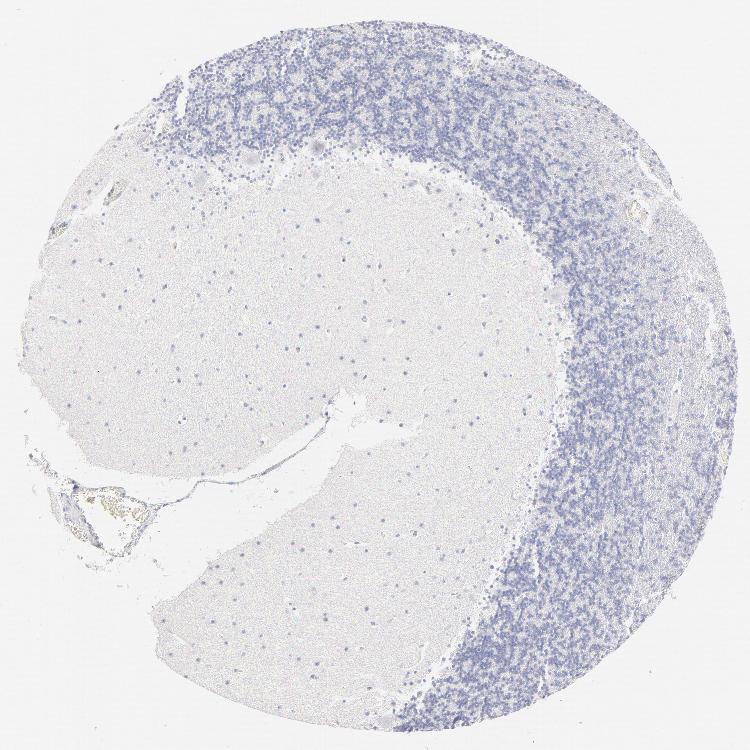

BRAIN CEREBELLUM Show tissue menu

CEREBELLUM - Expression summary

CEREBELLUM - Antibody stainingi

Antibody staining in the annotated cell types in the current human tissue is reported as not detected, low, medium, or high, based on conventional immunohistochemistry profiling in selected tissues. This score is based on the combination of the staining intensity and fraction of stained cells.

Each image is clickable and will lead to virtual microscopy that enables deeper exploration of all samples and also displays staining intensity scores, fraction scores and subcellular localization as well as patient and tissue information for each sample.

Antibody HPA003316Antibody HPA003479

Purkinje cells Not detectedNot detected

Cells in granular layer Not detectedNot detected

Cells in molecular layer Not detectedNot detected